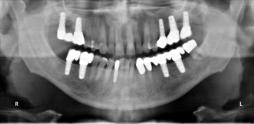

Beispiele für komplexe implantologische Versorgungen aus unserer Gemeinschaftspraxis

(Planung / Endversorgung -- als Röntgenaufnahmen)